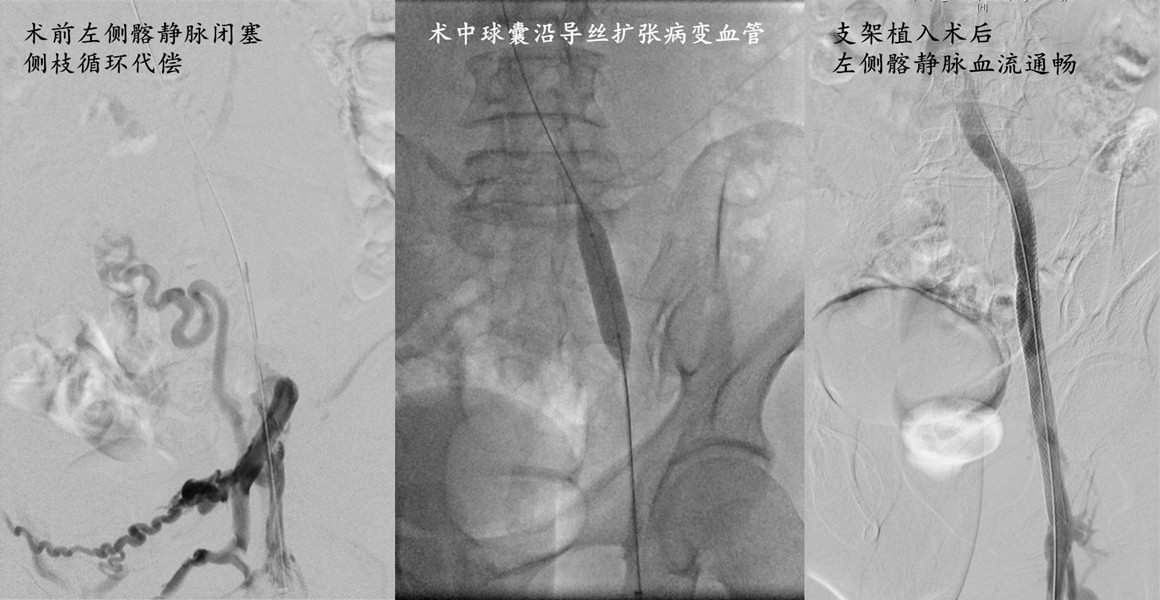

吴巍巍主任医师制定了药物消肿、抗凝,仔细换药,尝试开通闭塞静脉的方案。在DSA造影机下,血管外科医师仔细寻找左侧髂静脉通路,配合球囊扩张、支架植入,顺利开通了闭塞的左侧髂静脉,恢复了左下肢血流。20天后,陈伯伯的小腿肿胀明显缓解、溃疡成功愈合,出院后继续康复治疗。

图2 患者术后左侧髂静脉血流恢复